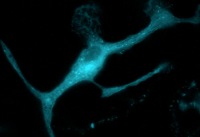

Somewhere in your brain, immune cells (like the one below) are on patrol, crawling around your neurons on the lookout for debris that’s piling up, bacteria that have snuck in, even neurons that are malfunctioning.

A microglia cell before activation. Image: Francesca Bartolini/Columbia University.

Before these cells, called microglia, can clear the debris or invaders, they must be activated—and in the process the long narrow cells undergo a dramatic change in shape, drawing up into a round, flat disk, like an amoeba.